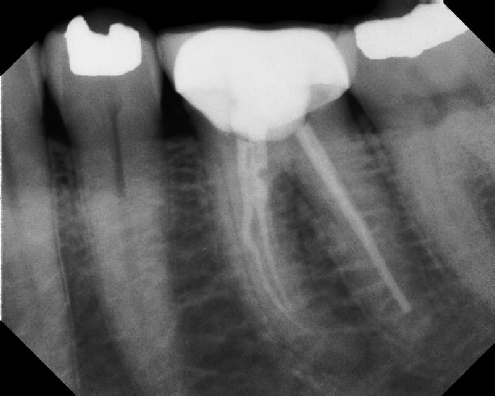

Root Canal Retreatment - Meriden 8 mos. recall Post-op Pre-op